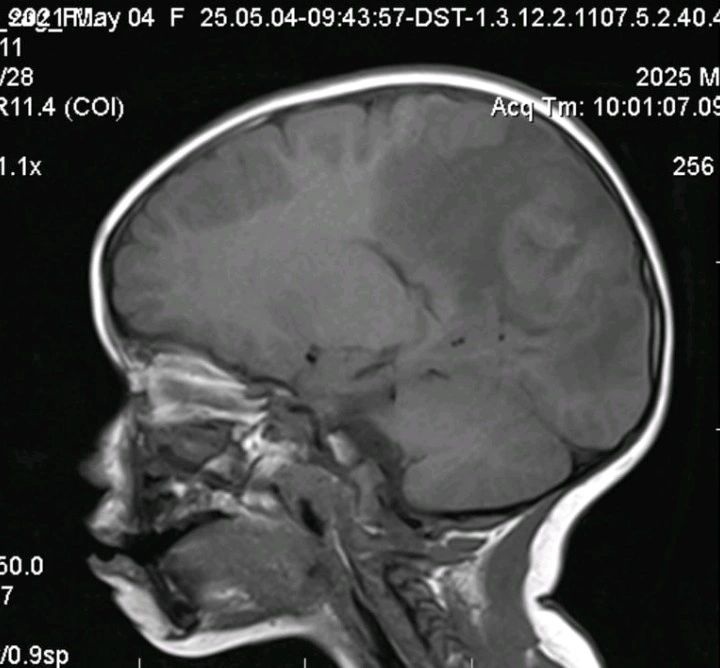

- 影像学检查: 脑部 MRI 显示明显的颅内占位伴水肿(见附图),高度怀疑为脑肿瘤。

🔪 【诊断陷阱与外科困境】 由于影像学表现极像肿瘤,且缺乏全身性或感染性体征,患儿接受了神经外科切除手术。 然而,术后病理结果却出人意料:中枢神经系统结核瘤(CNS tuberculoma)!